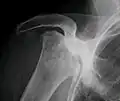

X-ray images of avascular necrosis in the early stages usually appear normal. In later stages it appears relatively more radio-opaque due to the nearby living bone becoming resorbed secondary to reactive hyperemia.[2] The necrotic bone itself does not show increased radiographic opacity, as dead bone cannot undergo bone resorption which is carried out by living osteoclasts.[2] Late radiographic signs also include a radiolucency area following the collapse of subchondral bone (crescent sign) and ringed regions of radiodensity resulting from saponification and calcification of marrow fat following medullary infarcts.

Radiography of total avascular necrosis of right humeral head. Woman of 81 years with diabetes of long evolution.